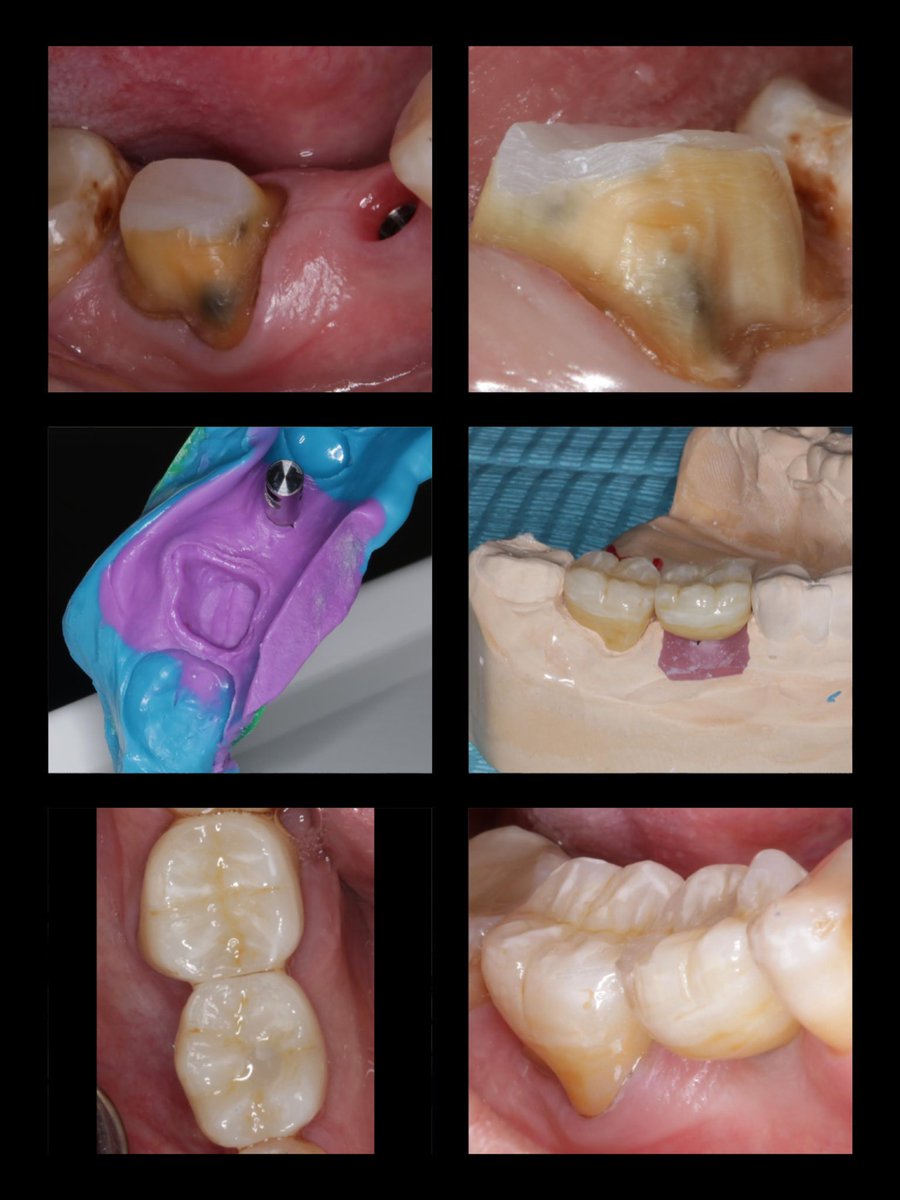

Zirconia crown on Endotreated #47 Implant supported crown on #46, The implant was placed by @alomar_ahmed